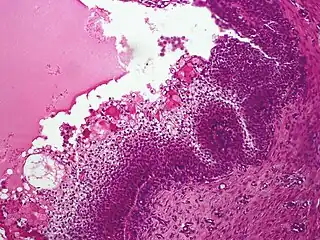

| Micrograph showing an acrospiroma. H&E stain. | |

Nodular hidradenoma, showing clear and polygonal cells with foci of eosinophilic material